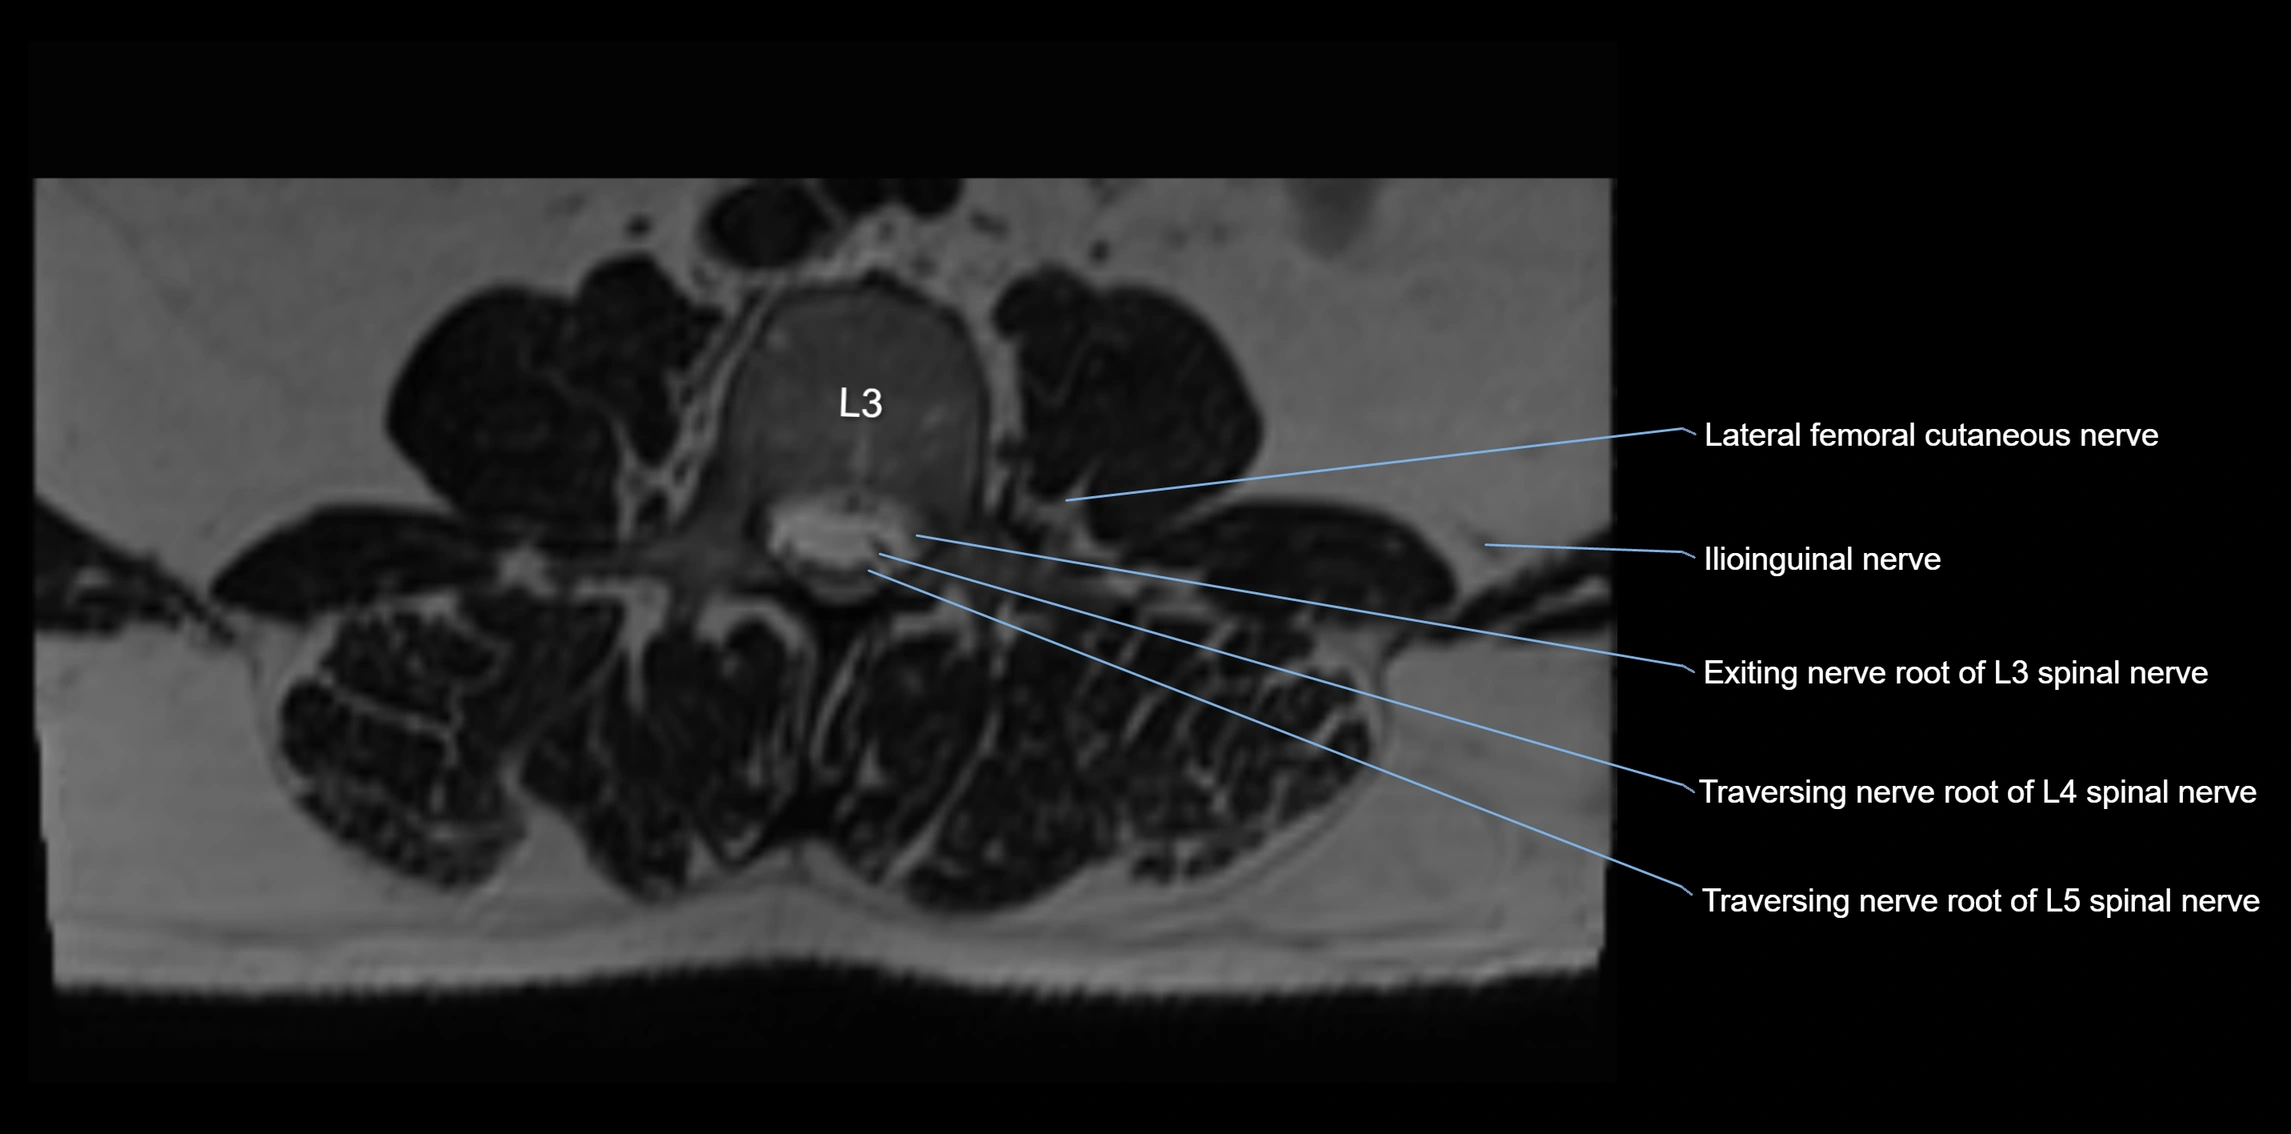

MRI image

image